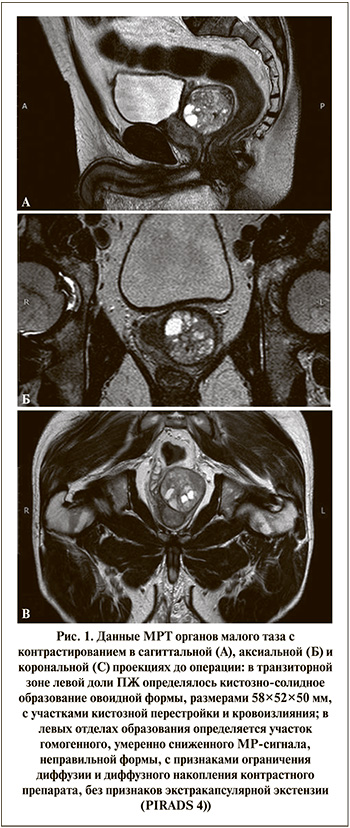

Пациент У. 62 лет поступил в урологическое отделение клиники ФГБОУ ВО СибГМУ Минздрава России (Томск) в плановом порядке в ноябре 2021 г. для выполнения биопсии ПЖ. На момент осмотра пациент предъявлял жалобы на частое мочеиспускание, ноктурию до 4 раз в сутки. Перечисленные жалобы беспокоили длительное время (3–4 года). Обратился к урологу поликлиники, где было проведено обследование: ПСА крови, ТРУЗИ ПЖ, МРТ органов малого таза с контрастированием, после чего с результатами обследования поступил для выполнения биопсии ПЖ. При поступлении: ПСА 11,9 нг/мл. По данным ТРУЗИ, объем ПЖ составил 94 см3, из левой боковой доли исходит образование, располагающееся между основанием ПЖ и шейкой мочевого пузыря, с одной стороны, и прямой кишкой, с другой. Образование размером 60×43 мм с множественными жидкостными включениями, максимально до 12×10 мм, с локусами повышенного кровотока в режиме ЦДК. По результатам МРТ в транзиторной зоне левой доли ПЖ определялось кистозно-солидное образование овоидной формы размером 58×52×50 мм, с участками кистозной перестройки и кровоизлияния; в левых отделах образования визуализировался участок гомогенного, умеренно сниженного МР-сигнала неправильной формы, с признаками ограничения диффузии и диффузного накопления контрастного препарата, без признаков экстракапсулярной экстензии (PIRADS 4) (рис. 1). Под контролем УЗИ 09.11.2021 выполнена промежностная мультифокальная и прицельная биопсия ПЖ. Было взято по шесть фрагментов из обеих долей, а также два фрагмента из новообразования в левой доле. Результаты гистологического исследования: узловая гиперплазия ПЖ, железисто-гладкомышечный вариант. Хронический простатит, фиброз стромы. Атрофия части ацинарных структур.